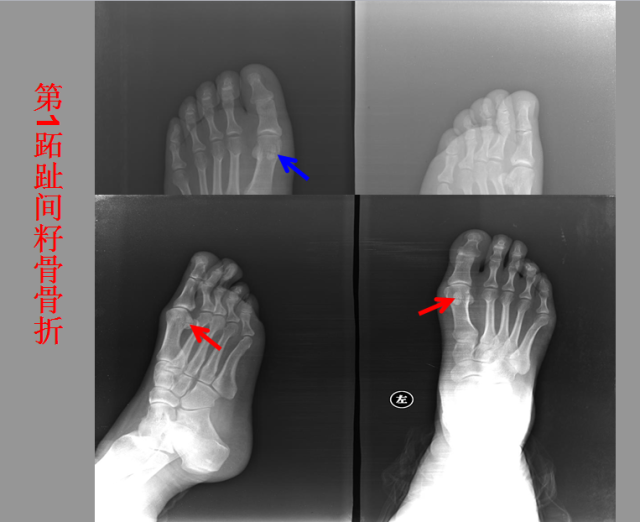

骨折篇

01

定义:骨折{Fracture}是指骨的完整性和连续性的折裂或粉碎。包括创伤性骨折、疲劳性骨折和病例理性骨折。 临床上以创伤性骨折*常见。